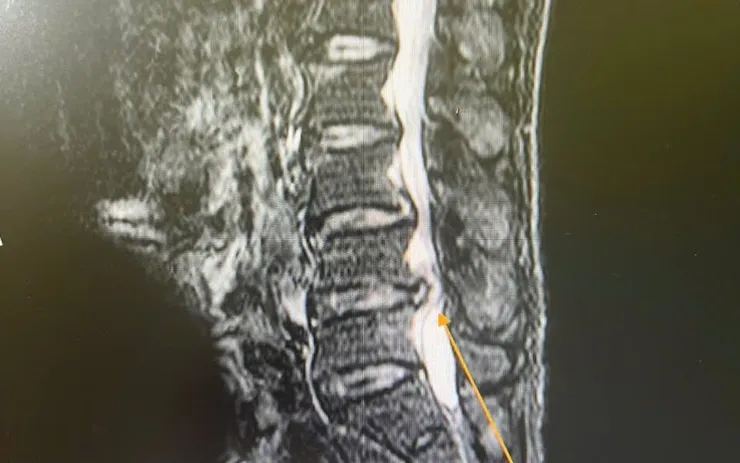

Qua thăm khám, các bác sĩ xác định bệnh nhân bị thoát vị đĩa đệm kèm hẹp ống sống và rối loạn cơ tròn - tình trạng có thể dẫn đến liệt vĩnh viễn nếu không can thiệp kịp thời. Bệnh nhân được chỉ định phẫu thuật.